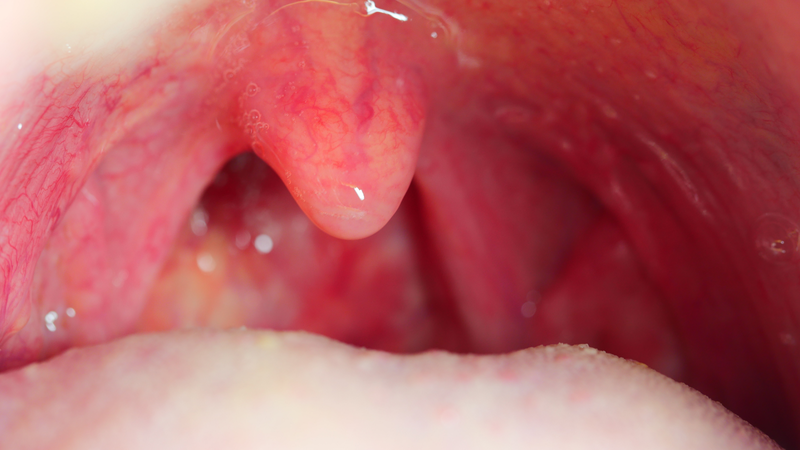

Amidan là một phần quan trọng trong hệ miễn dịch của cơ thể, giúp chống lại vi khuẩn và virus xâm nhập qua đường hô hấp. Tuy nhiên, không ít người gặp phải tình trạng amidan nổi cục thịt gây lo lắng và khó chịu. Đây có thể là dấu hiệu của một số vấn đề sức khỏe liên quan đến hệ hô hấp. Vậy amidan nổi cục thịt có nguy hiểm không?

Amidan nổi cục thịt là một hiện tượng bất thường ở vùng niêm mạc họng, thường khiến người bệnh cảm thấy đau rát, khó nuốt và thậm chí khó thở. Không chỉ gây cảm giác khó chịu kéo dài ở cổ họng, tình trạng này còn ảnh hưởng lớn đến khả năng giao tiếp và các hoạt động sinh hoạt thường ngày, làm suy giảm chất lượng cuộc sống.

Amidan nổi cục thịt có thể là biểu hiện của nhiều bệnh lý khác nhau liên quan đến hệ hô hấp, do đó việc xác định mức độ nguy hiểm của tình trạng này không hề đơn giản. Trong một số trường hợp, tình trạng nổi cục thịt có thể là dấu hiệu của những vấn đề nhẹ như viêm nhiễm thông thường, nhưng cũng không loại trừ khả năng cảnh báo các bệnh lý nghiêm trọng, đặc biệt là ung thư vòm họng. Người bệnh cần đặc biệt chú ý đến các triệu chứng đi kèm và sớm thăm khám để được chẩn đoán chính xác, tránh chủ quan dẫn đến hậu quả đáng tiếc.